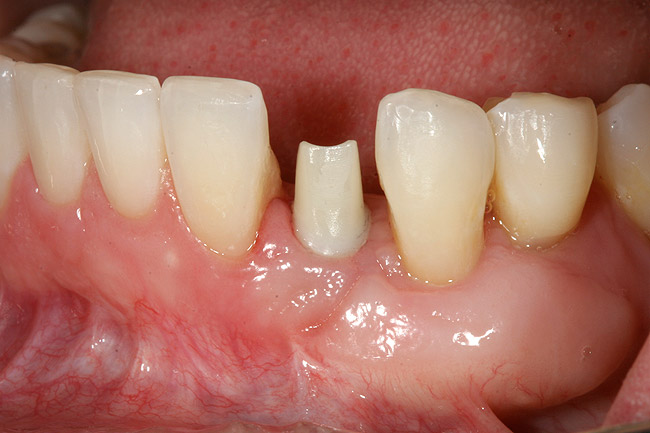

Figure 2  A preoperative retracted anterior view of the failing implant in the site of tooth No. 22.

Figure 2

A 28-year-old Caucasian female presented to the periodontist with a complaint of a mobile implant in the site of tooth No. 22 (Figure 2 and Figure 3). The patient had a congenitally missing tooth No. 23. No. 22 had erupted into site No. 23, leaving a vacancy at site No. 22, and was the reason for the original implant at site No. 22.